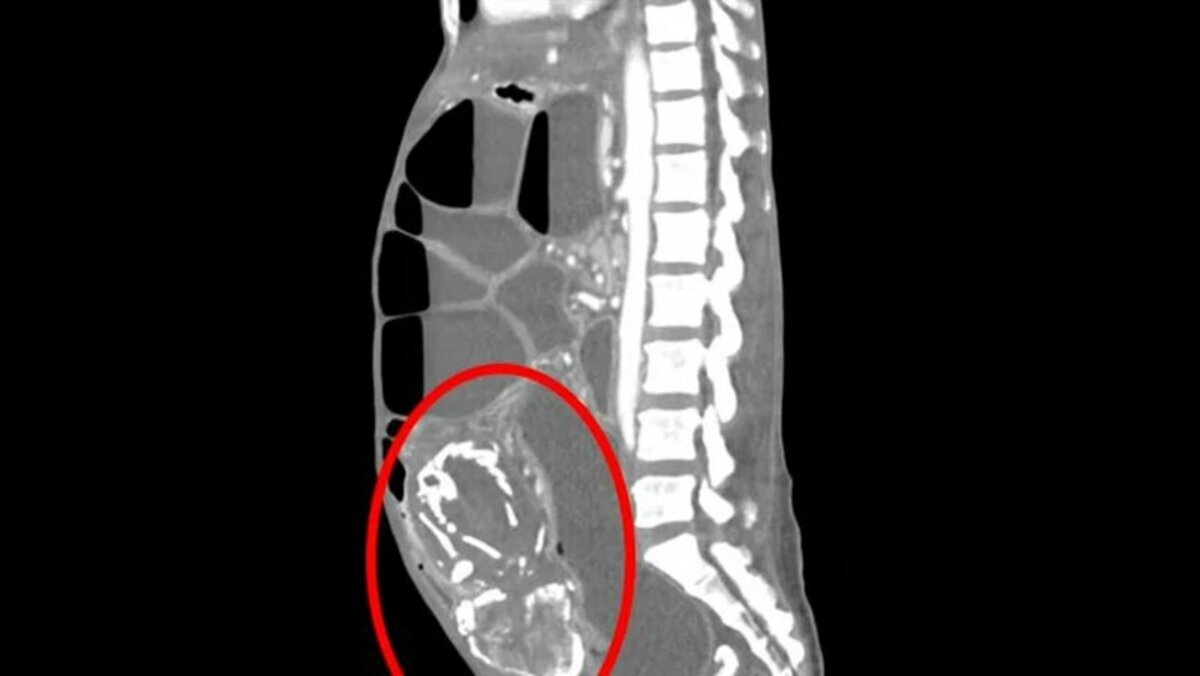

Он сдавил погибшей тонкую кишку. Окаменевший плод ребенка, который в себе носила жительница Конго, привел к ее смерти из-за острого голода. Отмечается, что он сдавил ей тонкую кишку, сообщает Daily Mail. О нестандартном случае рассказали сотрудники Медицинского университета SUNY Upstate. По их словам, жительница Конго обратилась к медикам американского города Нью-Йорк с жалобами на спазмы в брюшной полости.

Так, в ходе диагностики был обнаружен окаменевший плод ребенка, который был кальцинирован. Отмечается, что пациентка отказалась от предложенного лечения, смерть наступила от недоедания. Также врачи рассказали, что во время своей 9-ой беременности женщина посетила клинику в лагере беженцев в Конго сообщив, что ее ребенок не подает признаков жизни. Медики сказали ей, что у плода нет сердцебиения, а также порекомендовали ей вернуться через две недели, если не будет самопроизвольного выкидыша. Однако она так и не вернулась из-за обвинений окружающих в умервлении плода. Ранее Readovka писала о том, что десятки тысяч американцев вышли на митинги после отмены конституционного права об абортах.